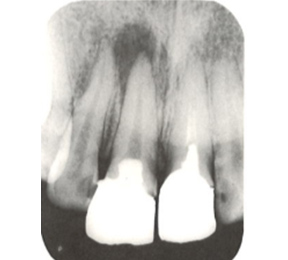

実際のケースを

ご説明していきます

こちらのレントゲン写真を見てください。どちらかの歯医者さんで神経を取っています。根管に入れる薬は白く映ります。赤矢印部分です。一番右側が模式図ですが、青い部分が薬、根っこの先の赤点が化膿している部分です。

薬がほとんど入っていないのがわかります。黄矢印部分です。青矢印まで薬が入らないといけないのですが、全く入っていません。その結果、根っこの先が黒くなっています。膿が貯まって化膿すると黒く写ってくるのです。

よく手抜きをしたのですかと聞かれます。おそらく手抜きではありません。担当した先生はベストを尽くしたと思います。ベストを尽くしても、抜髄は大変難しいので、これが精一杯だったのでしょう。

別な歯科医院で治してもらいました。薬が根の先まで入っているのがわかります(黄矢印)。 根尖の黒い影が消失しています(赤矢印)。骨が再生すると白く写るようになります。

①の写真はどちらかの歯医者さんで神経を取ってもらったレントゲン写真です。根っこの中に薬が全く入っていません。

②の模式図で青く描かれている部分が薬です。

根の先を見ると小豆ぐらいの大きさの黒い影が見えます。根の中でばい菌が繫殖し感染を起こすとこのような黒い影ができます。黒い影の部分は膿(ウミ)が貯まっています。こうなると腫れて痛みが出てくるのです。

③、④の写真はそれを治した後のレントゲン写真とその模式図です。白く映っている薬が根の先まできちんと入っているのが確認できます。そして根の先にあった黒い影が消えているのが分かります。根の先の炎症が治って、骨が再生すると白く映るのです。

実はこのケース、歯医者さんの神経を取る治療でこのような根っこの病気になってしまったのです。そこでこの患者さんは神経を取った歯医者さんではなく、別の歯医者さんに受診して、根っこの治療をして治したのです。